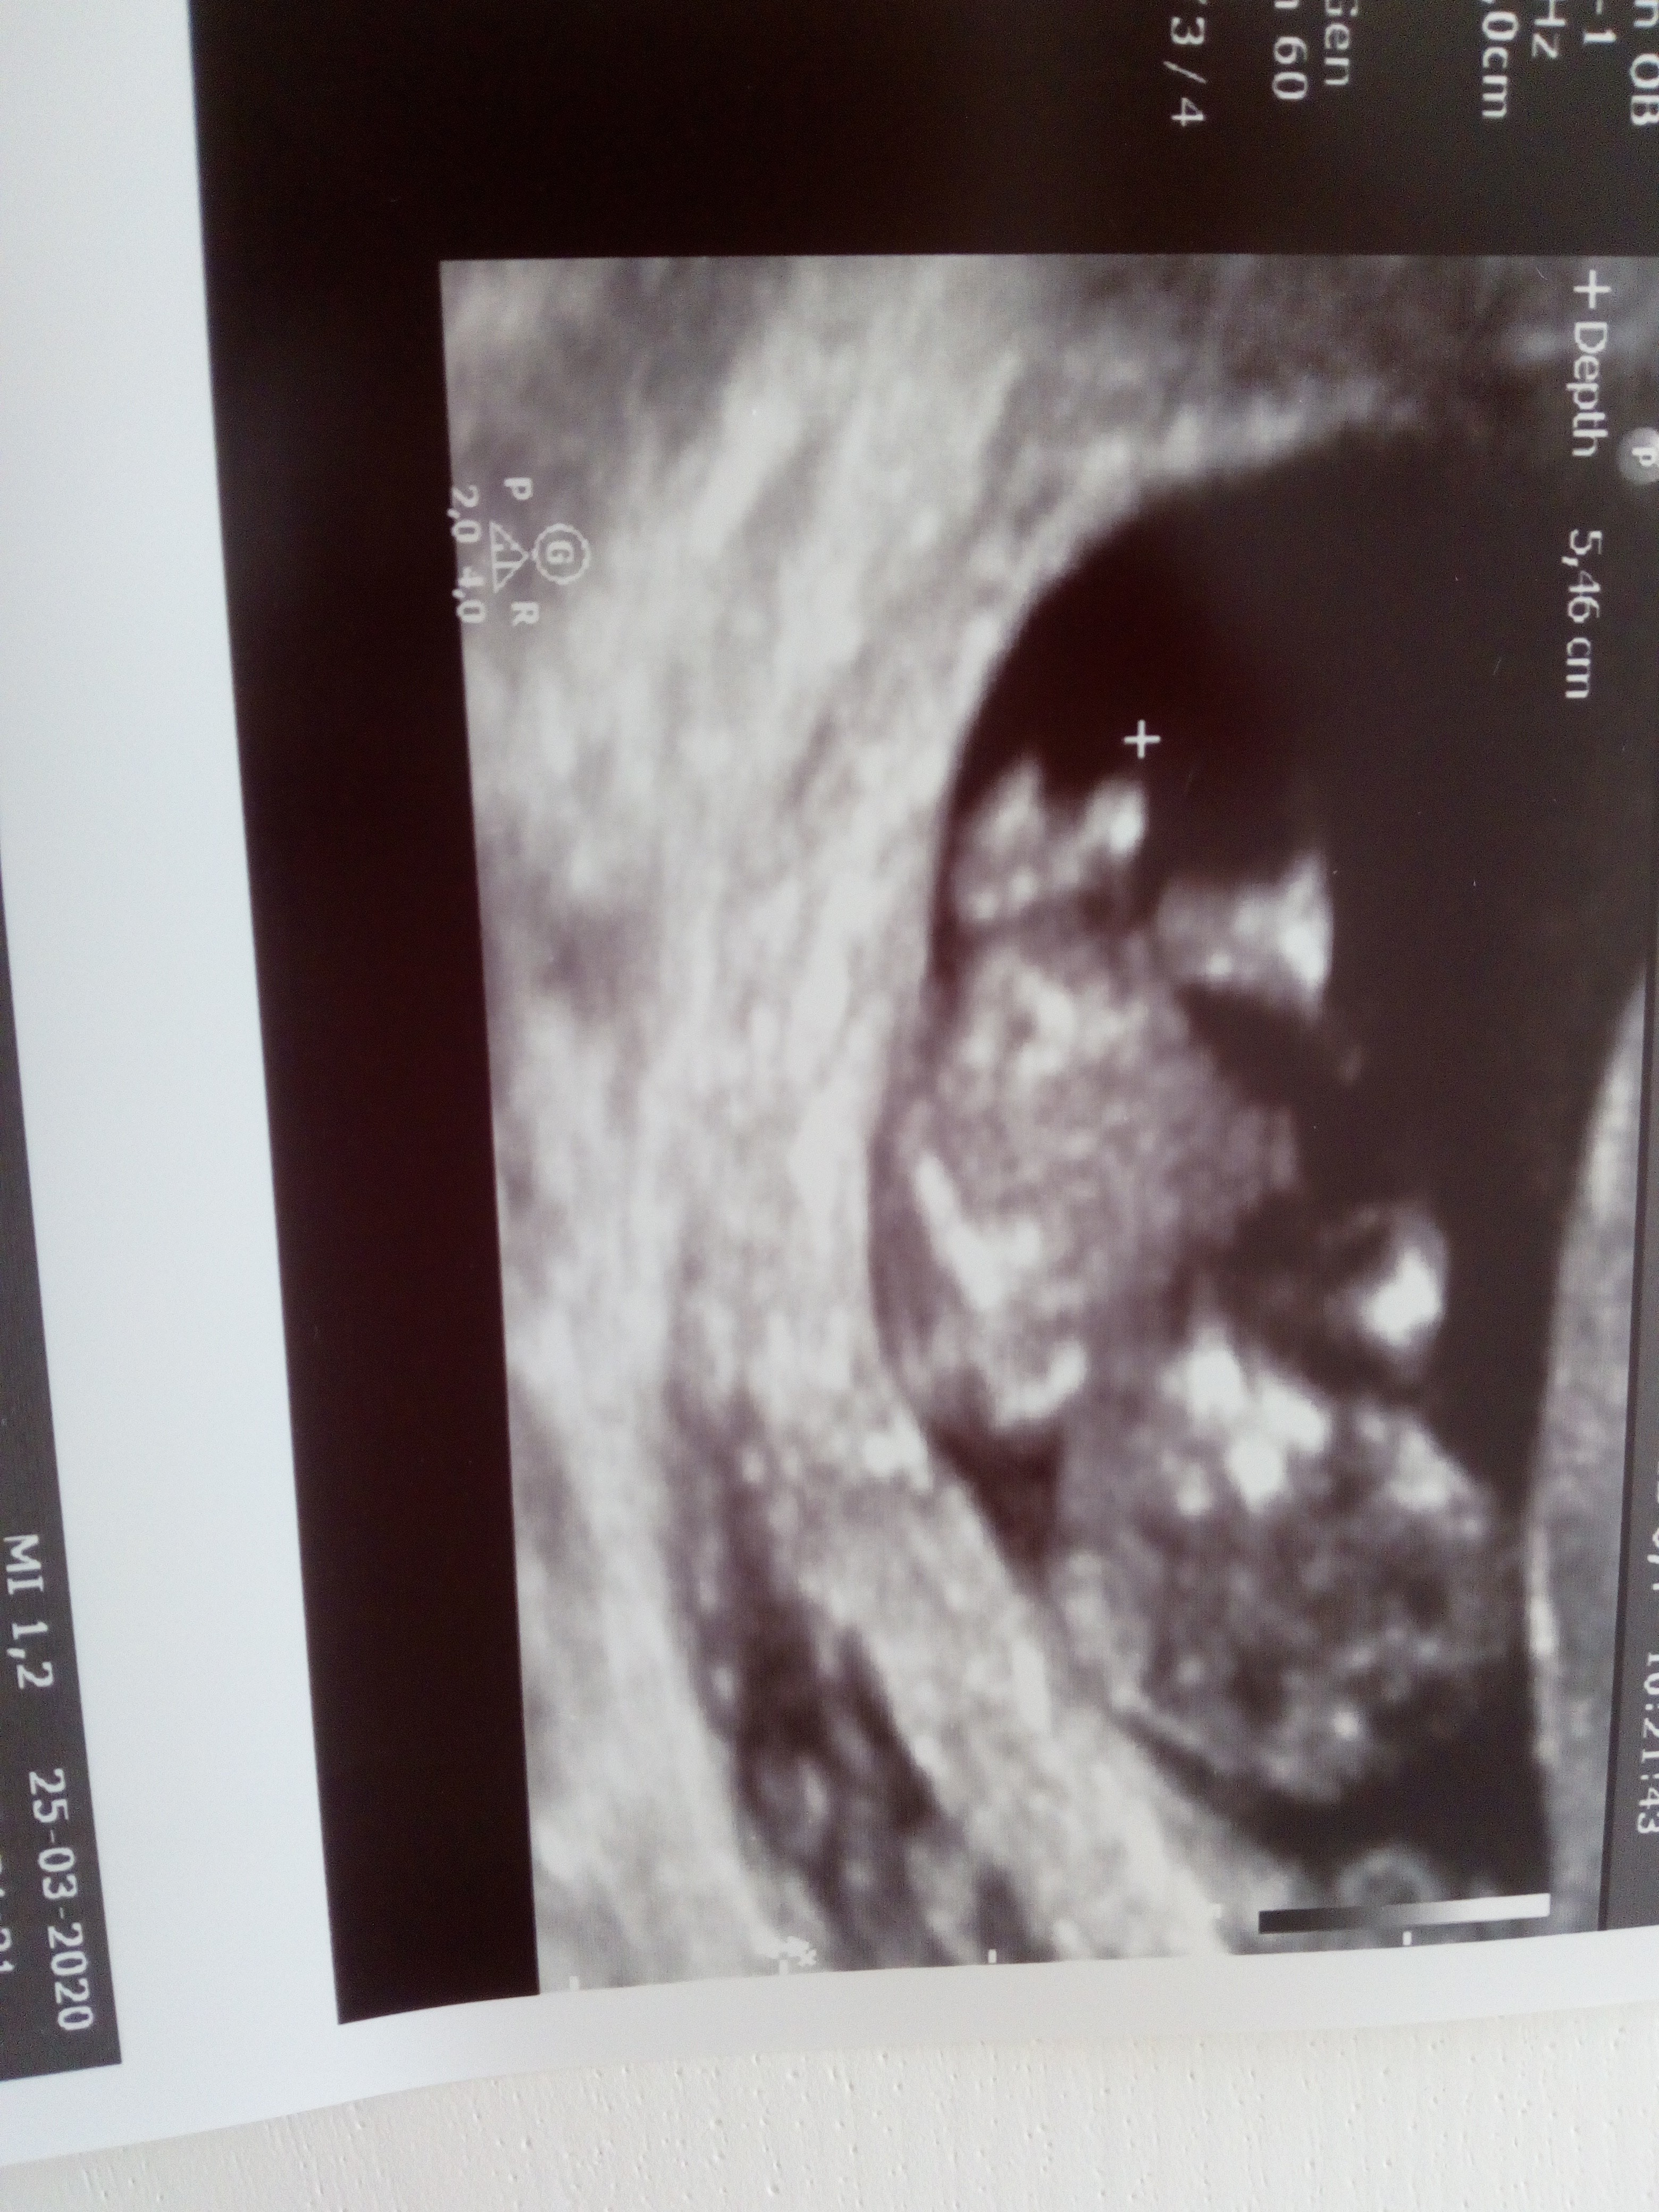

Tez tak czytałam, może jeszcze się okaże inaczej. Z tym, ze ten „wypustek” to wyglądał konkretnie, wręcz ewidentnie [emoji23] Ponoć u chłopców skierowany jest do góry a u dziewczynek ku dołowi [emoji846]

Dokładnie. Tak u mojego synka to wygląda jest nawet zaznaczone. Duze, sterczace i jakby takie zakończone kulką

Załączniki

• IMG_20200325_104927.jpg

IMG_20200325_104927.jpg

2,7 MB · Wyświetleń: 105